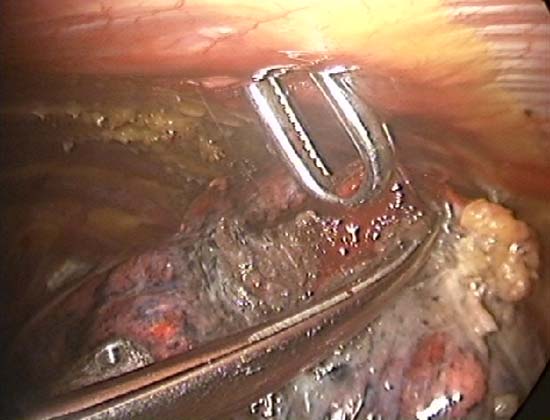

The TissueLink device does not perforate or cut into tissue (in contrast to conventional electrocautery). Instead, the surface of the tissue is painted with the device, which first coagulates and then shrinks the lung tissue (Figure 3). The surgeon then divides the coagulated tissue with scissors (Figure 4). Compared with conventional electrocautery, the TissueLink device usually leaves the resection bed more hemostatic and pneumostatic.

Slightly longer time is needed for resection using the TissueLink device. It is excellent in sealing small (1mm or less) bronchioles in the resection bed. The floating ball device should be applied directly over the bronchiole for one to two minutes to accomplish this. The TissueLink device, by nature of the technology, generates less smoke than conventional electrocautery. However, a small amount of steam is inevitable, and it is advisable to keep a sucker (a conventional Yankauer sucker works best) close to the surgical field, which also may be used to exert counter-traction on the lung tissue to facilitate dissection (Figure 5). As with all potential cancers, specimens should be placed in a bag before they are removed through a port site (Figure 6).